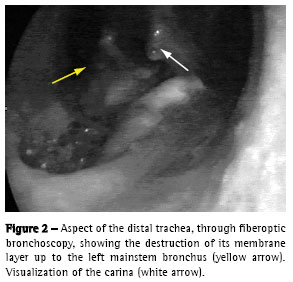

We performed upper digestive endoscopy, which revealed a large fistula between the esophagus and the left bronchus, although the device passed without difficulty (Zagar class 3b(8)). The esophageal mucosa was friable with intense deposits of fibrin. A nasogastric tube was positioned in the second portion of the duodenum (Figure 1).

The control chest X ray, after upper digestive endoscopy, revealed left pneumothorax. Left thoracic drainage was performed with immediate lung re-expansion. In the fiberoptic bronchoscopy, we observed an area of destruction of the distal trachea, carina and left bronchus of approximately 3 x 1.5 cm (Figures 2 and 3), as well as exposure of the mediastinal tissue, together with de-epithelization and retraction of the epiglottis and right vocal chord.